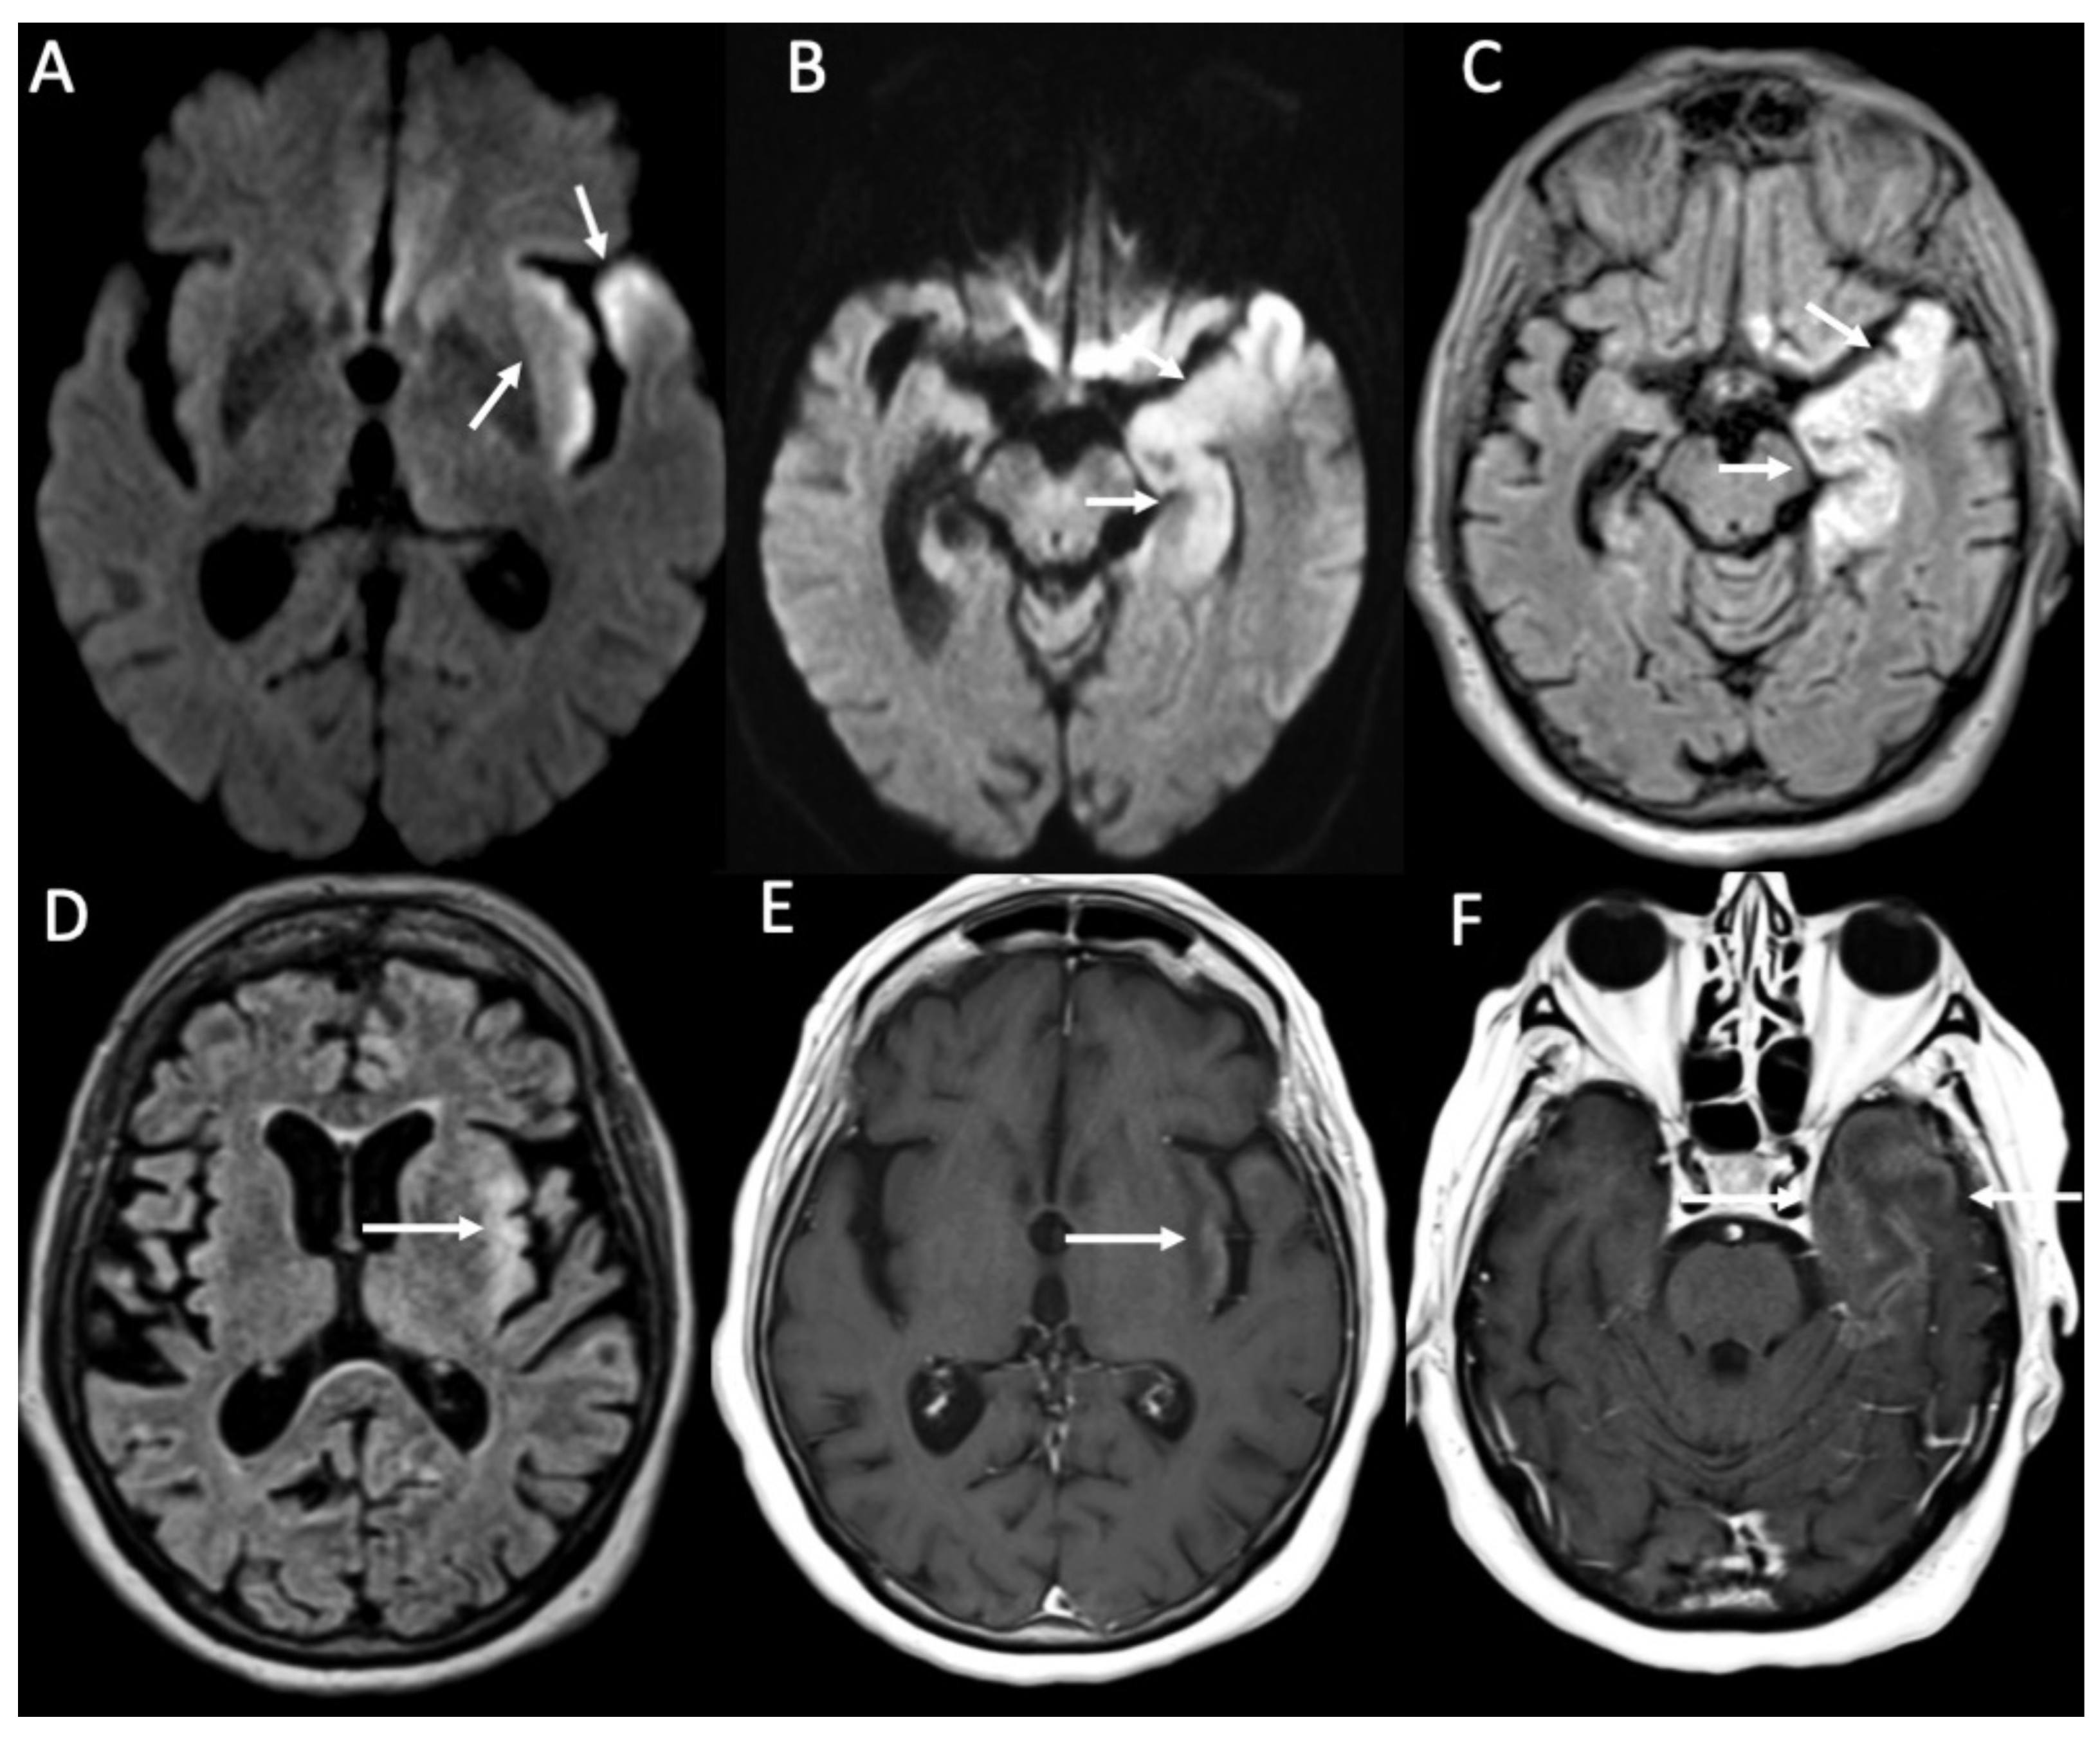

In HSE, involvement of the temporal lobe and limbic system is typical, and it is probably related to the intracranial spread of HSV-1 through meningeal branches of the trigeminal ganglion [49]. In the early stages, CT can be unremarkable [50]. Later, it may show hypodensity in the temporal and insular cortex and cingulate gyrus, which is bilateral and asymmetric. On MRI, there is restricted diffusion of the cortex in the same regions, which appear hypointense on T1 and hyperintense on T2 and FLAIR sequences (Figure 13) [51]. In the subacute phase, there is swelling of the involved areas, and leptomeningeal and/or parenchymal enhancement may occur as well as hemorrhagic foci (Figure 14) [25]. Rarely can HSV-1 determine sudden hearing loss without neuroimaging findings of encephalitis. On MRI, the only finding is enhancement of the acoustic nerves (Figure 15) [52].

Figure 13.

Axial DWI (A,B), FLAIR (C,D), and enhanced T1 (E,F) show fronto-temporo-insular signal alterations due to Herpes virus simplex type 1 encephalitis, which determines restricted diffusion (arrows in A,B), hyperintensity on FLAIR (arrows in C,D) and gyriform contrast enhancement (arrows in E,F).

Figure 14.

Axial T2 (A), FLAIR (B), susceptibility-weighted imaging (C), and enhanced T1 (D) show hyperintensity of the temporal lobe on T2 and FLAIR (arrows in A,B) in a patient with Herpes virus simplex type 1 encephalitis in the subacute phase. There are also some hemorrhagic foci (arrowheads in C) and contrast enhancement (arrow D). Note also concomitant temporo-polar arachnoid cyst (asterisk in A–D).

VZV may determine varicella and herpes zoster, and transmission requires close contact between individuals [53]. After primary infection, the virus may be latent for years in nerve ganglia (especially the trigeminal) and reactivate after years, usually in the elderly or in case of debilitating conditions [54]. Meningitis is the most common CNS complication of VZV, but it can also present with Ramsay–Hunt syndrome (RHS), Herpes-zoster ophthalmicus (HZO), and focal cerebral arteriopathy (FCA). VZV meningitis imaging is that of lymphocytic meningitis and may be associated with cerebellitis, which is better evaluated with MRI and appears as diffuse cortical signal alteration, which is hypointense on T1, hyperintense on T2 and FLAIR sequences, and may show enhancement and cortical swelling, especially in advanced phases [55]. Clinically, RHS involves the geniculate ganglion, with VII and VIII cranial nerve palsy. CT may be unremarkable, whereas MRI shows abnormal enhancement of these nerves, which is linear and smooth (Figure 16) [56]. Rarely, on MRI, signal alterations in the trigeminal nucleus in the brainstem may be found, which appear hyperintense on T2 and FLAIR and show contrast enhancement [57]. In HZO, there may be extensive involvement of the optic system, including optic nerves and chiasm, which appear hyperintense on T2 and FLAIR sequences and may show contrast enhancement [58]. FCA is a late complication that mainly affects the pediatric population and immunocompromised adults [59]. It affects proximal anterior circulation, and in particular of middle cerebral arteries, which may show intense wall enhancement (detectable on vessell-wall imaging), with small infarcts (Figure 17) in the lenticulostriate territory [60].

Figure 16.

Axial enhanced T1 shows enhancement of the left acoustic nerve and homolateral facial nerve (arrows) in a patient with Ramsay–Hunt syndrome.

Figure 17.

Axial computed tomography shows a small hemorrhage in the subcortical region of the left parietal region (arrow) in a patient with varicella zoster virus encephalitis.